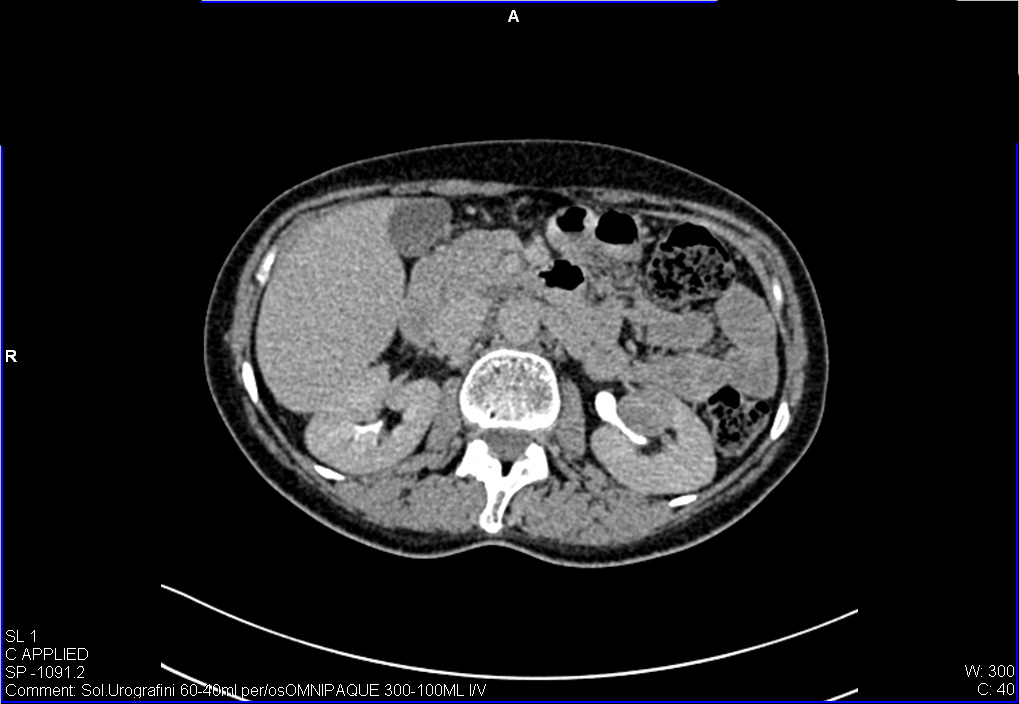

Женщина средних лет, жалоб нет.

УЗИ почек - малый рак. Small RCC.

Подозревается TCC

Позвонили пациентке, она сделала КТ - новообразование подтверждено.